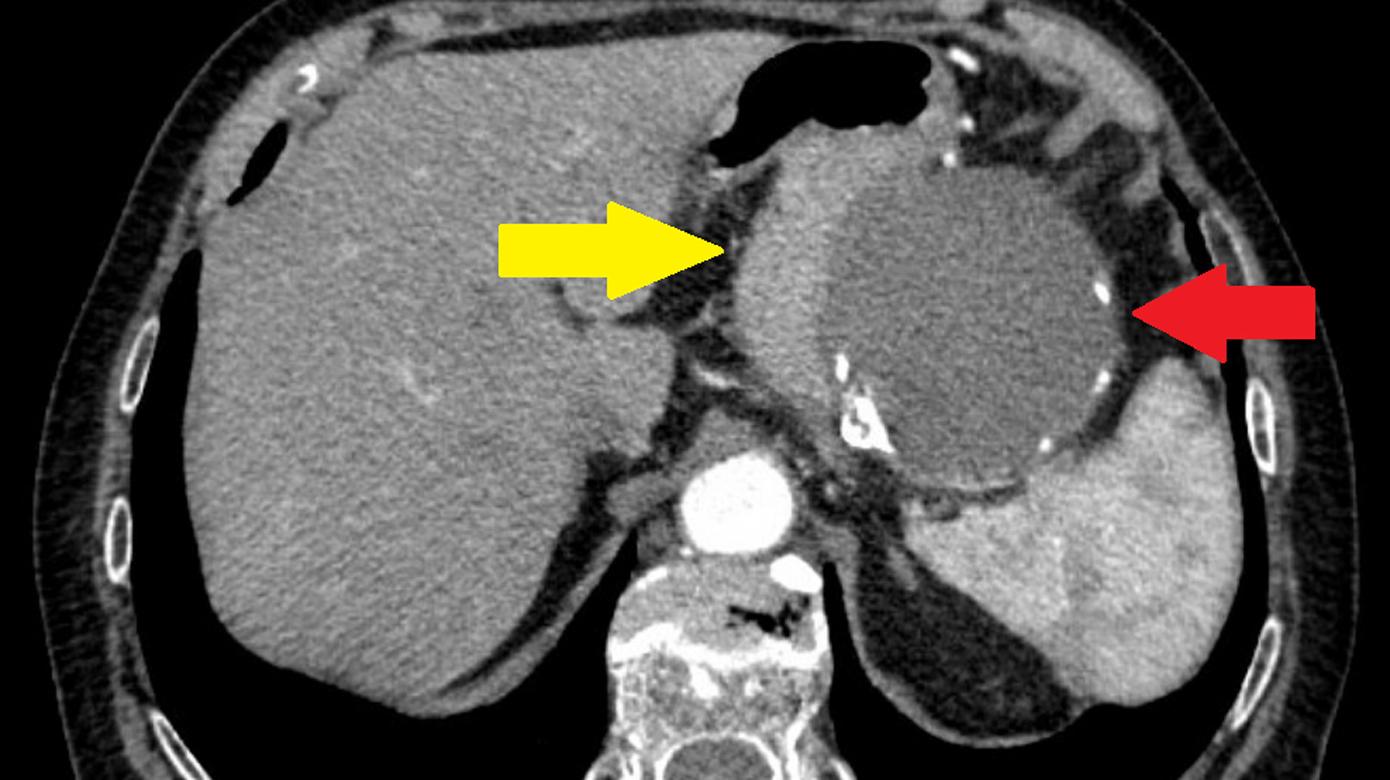

Man valgte at bestille en CT af abdomen mhp. visualisering af bagvedliggende patologi. CT’en viste et gigantisk a. lienalis-aneurisme på 9 cm (Figur 1). Patienten blev efterfølgende henvist til karkirurgerne, som foranstaltede coiling (endovaskulær embolisering) af aneurismet.